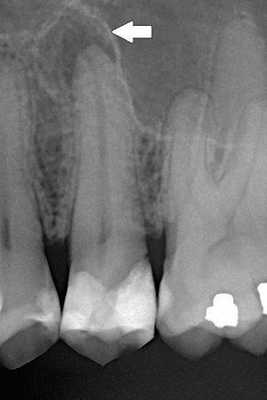

В поликлинике "Наша Клиника-Дент" проведено визиографическое обследование свищевого хода, предварительно в него был введён гуттаперчевый штифт для уточнения локализации воспалительного процесса. Выявлен очаг воспаления в области корней 17 зуба. Также обнаружен участок повышенной плотности, по конфигурации соответствующий фрагменту инструмента в мезиально-щёчном корне 16 зуба.

После снятия коронки и старой пломбы. Видно кариес, который мог быть дополнительным источником инфекции.